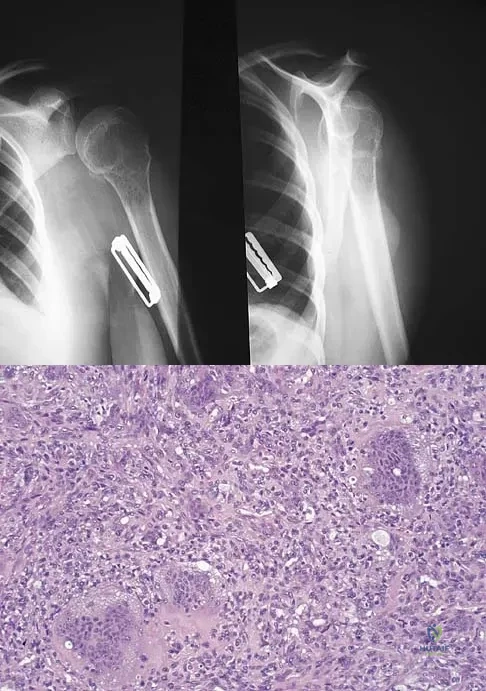

Question 32

In 1980, a 32-year-old woman was found to have right breast mass, and a biopsy revealed adenocarcinoma. She underwent a mastectomy at that time, with no other treatment. Five years later, she noticed a lump in the left breast and underwent a left mastectomy. Seven lymph nodes were positive. In 2006, she now reports hip and thigh pain for the past 3 months. Figures 69a and 69b show AP and lateral radiographs of the femur. A bone scan shows a solitary lesion. Following radiographic staging, what is the next most appropriate step in management?

Explanation